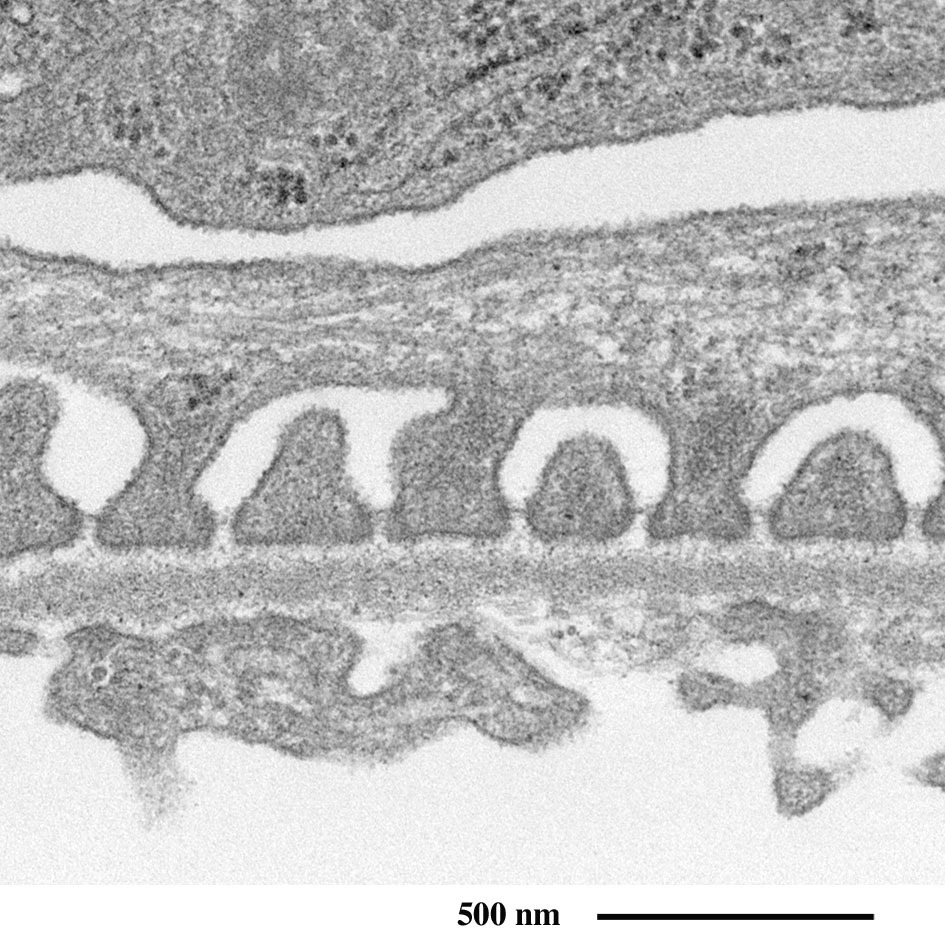

互いに隙間を埋める足突起

(拡大像)

糸球体の有窓毛細血管

(全周を足細胞の突起に囲まれた血管壁の横断面)